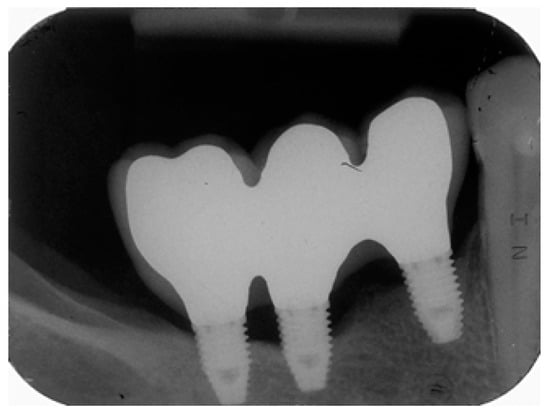

Risk scores are presented in Figure 2 and Figure 3. These scores can be used to obtain predictions for individual patients. As an example, we will examine a 59 year-old female with no history of periodontitis who was a non-smoker and who was rehabilitated with a three-unit implant-supported rehabilitation (three implants of 7 mm in length, positions #44–#46) that were restored using metal–ceramic material. At baseline (one year of follow-up) bacterial plaque and bleeding were present, and the bone level was located on the implants’ coronal third (Figure 2), which produces a total score of 8 points and puts her in the very high-risk profile. Peri-implant disease was diagnosed after 58 months on implant #45 due to the presence of peri-implant pockets of 5 mm and a three thread marginal bone loss (Figure 3).

Figure 2.

Baseline periapical radiograph (at one year of follow-up) from a 59 years old female patient with no history of periodontitis who was a non-smoker, rehabilitated with a three-unit implant-supported rehabilitation [three implants of 7 mm in length, positions #44–#46; Risk points = −1 due to adjacent implants or teeth present) restored using metal–ceramic material (Risk points = 2). Bacterial plaque (Risk points = 2) and bleeding (Risk point = 2) were present, and the bone level was located on the implants’ coronal third. Due to the presence of bacterial plaque and the presence of adjacent implants or teeth, 3 risk points were added. A total score of 8 points was registered for this patient which corresponded to the very high-risk group.